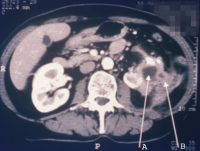

Diagnostisch spielen Sonographie und Computertomographie die entscheidende Rolle: Zumeist fallen die Veränderungen als diffuse Raumforderung auf (Abbildung 20).

Beim Fehlen einer entzündlichen Symptomatik wird differentialdiagnostisch nicht selten sonographisch die Diagnose Tumorverdacht gestellt.

Beispielhaft die bildgebende Diagnostik und das Organpräparat bei einem Patienten mit XGP (Abbildung 21). Hier führte das intraoperative Schnellschnittergebnis Tumor zur Nephrektomie.